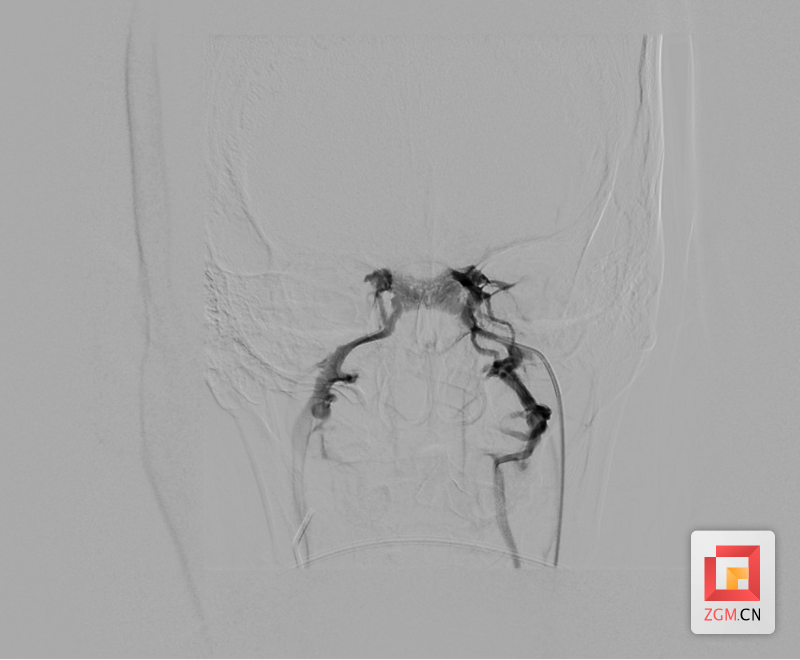

医务人员结合钟女士皮质醇变化及大剂量地塞米松抑制实验结果,综合考虑倾向于ACTH依赖性库欣综合征,为进一步明确其ACTH来源以指导后续诊疗,经医院多学科会诊后,医院微创介入团队决定为患者实施岩下窦静脉采血术进行精准诊断。

经微创介入团队实施岩下窦静脉采血术,采血结果经过检验提示为岩下窦静脉ACTH含量明显高于外周静脉血含量,明确为中枢性来源,遂转入神经外科行垂体瘤切除术。术后患者恢复良好,激素水平及皮质醇节律均恢复正常。